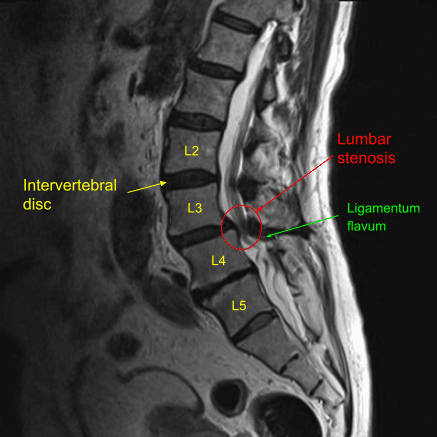

A patient presented to our clinic with signs and symptoms of severe lumbar stenosis. Surgery was recommended to decompress his lumbar spine after failure of conservative treatment measures.

Sagittal view of pre-operative Lumbar Spine MRI

Ligamentum flavum was severely hypertrophied correlating with the preoperative imaging. Once verified it was complete, the bed was air planed and the tubular retractor was angled to the left side contralateral over the top. Laminotomy was performed on the left side at L4-L5. Dura was carefully protected with cottonoids while contralateral hypertrophied ligamentum flavum was resected.